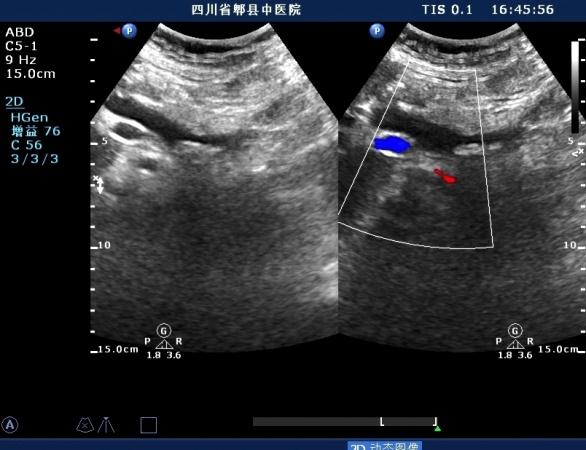

超声如图:胆总管及肝内胆管扩张,呈“平行管征”,胆总管胰腺段可见疏松强回声团堆积,后方可见淡淡声影,左肝外叶胆管内亦可见数个强回声团堆积,后方伴声影。 肝脏及胆总管

扩张的左肝内胆管

左肝内胆管结石